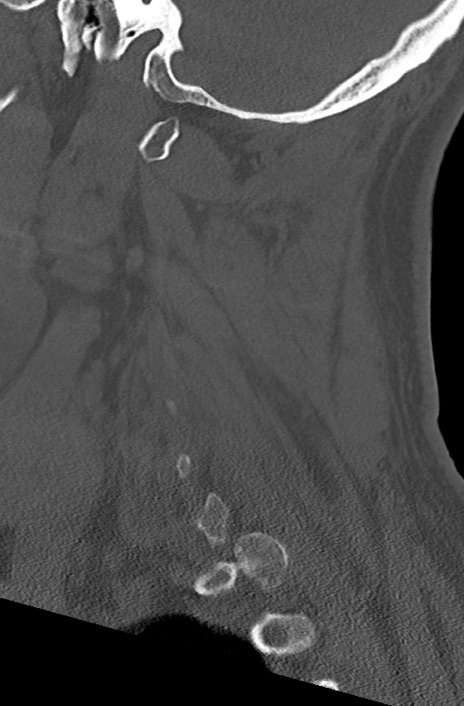

【整形】TIPS症例7 頚椎CT(矢状断像)

頚椎CT

矢状断像と横断像